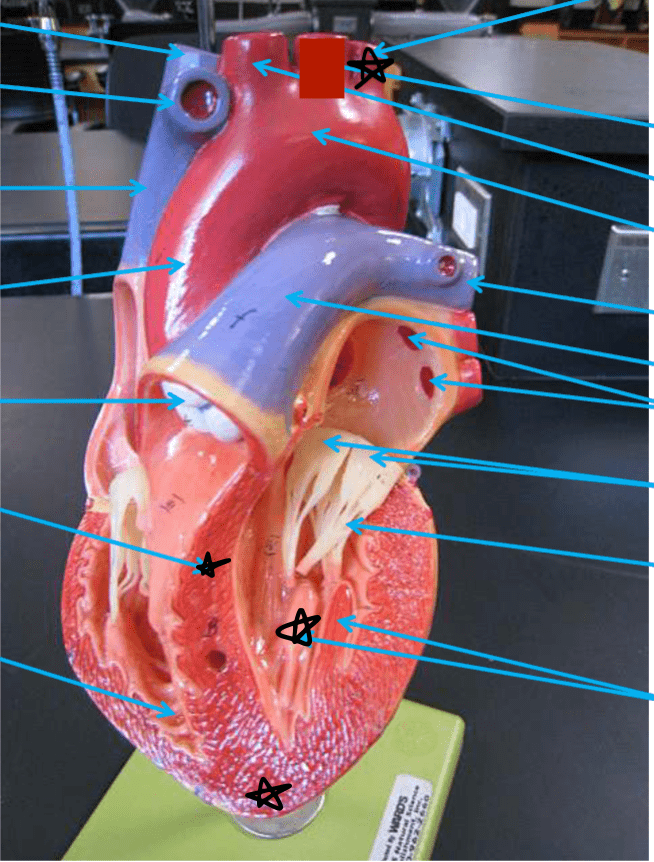

Label the structures that are starred.

Left subclavian artery

Interventricular septum

Papillary muscle

Apex of the heart

List all of the structures that are starred.

Aortic arch

Superior Vena Cava

Pulmonary artery

Anterior interventricular branch of the left coronary artery

What is this on the ventricle wall?

Trabeculae carneae

List the structures with a star.

SA node

Fossa ovalis

AV node